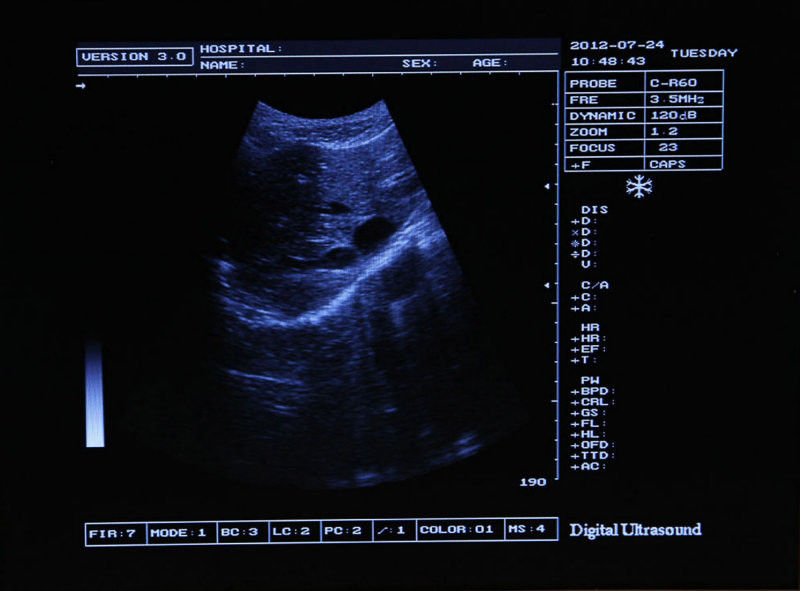

Full Digital Ultrasound Ultrasonic Scanner System 7.5 Mhz Linear Probe 3D image 190891058744

Model: RUS-9000B

Image mode: B, B/B, 4B, B+M, M

Display: 10-inch SVGA high resolution monitor